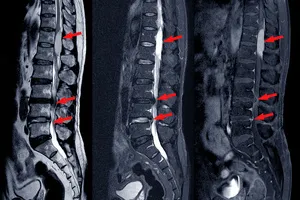

4. 추간판 탈출증 (디스크)

추간판 탈출증, 즉 디스크는 척추뼈 사이의 디스크가 튀어나와 신경을 압박하여 허리 통증을 유발하는 질환입니다. 무리한 운동, 잘못된 자세, 장시간 앉아 있는 등의 생활 습관이 원인이 될 수 있습니다. 허리 통증 외에도 다리 저림, 감각 이상 등의 증상이 나타날 수 있으며, 허리를 숙이거나 뒤로 젖힐 때 통증이 심해집니다. 치료는 약물 치료, 물리치료, 주사 치료 등 보존적인 방법부터 미세 현미경 수술, 내시경 수술까지 다양하며, 환자의 상태에 따라 적절한 치료 방법을 선택해야 합니다. 평소 바른 자세를 유지하고, 규칙적인 운동을 통해 허리 건강을 관리하는 것이 중요합니다.

5. 척추관 협착증

척추관 협착증은 척추관이 좁아져 신경이 눌리면서 발생하는 질환으로, 허리 통증과 함께 다리 저림, 보행 시 통증이 심해지는 것이 특징입니다. 장시간 서 있거나 걸을 때 증상이 악화되는 경우가 많습니다. 척추관 협착증은 노화, 퇴행성 변화 등 다양한 원인에 의해 발생하며, 조기 진단과 치료가 중요합니다.